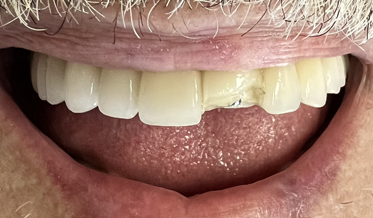

Redefining What Is Possible: Treating Function and Enhancing Esthetics Using a Risk Management System

Kris Swanson, DDS; and Leon Hermanides, CDT